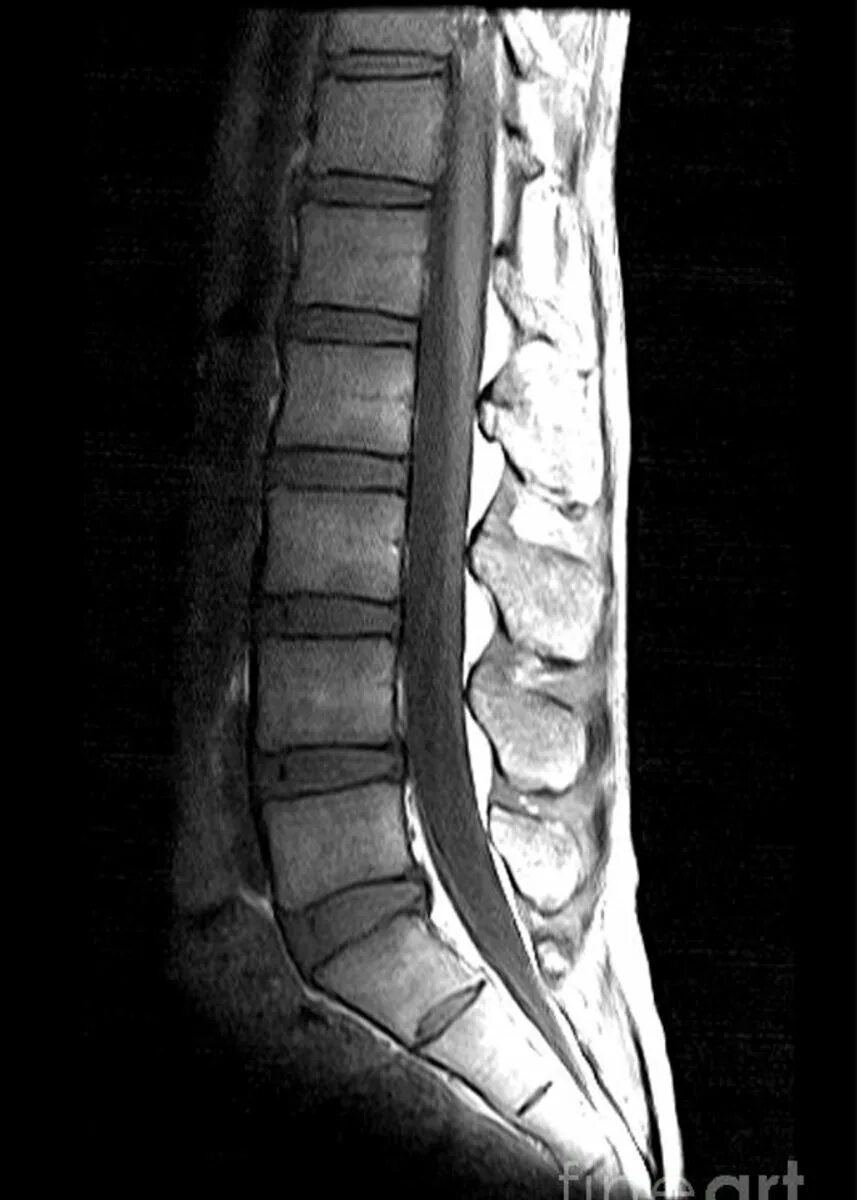

Spine mri